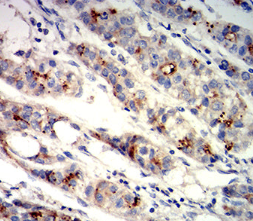

GPC3 Mouse Monoclonal antibody[2C7E9]

Species Reactivity :   Human

IHC    1/200-1/1000